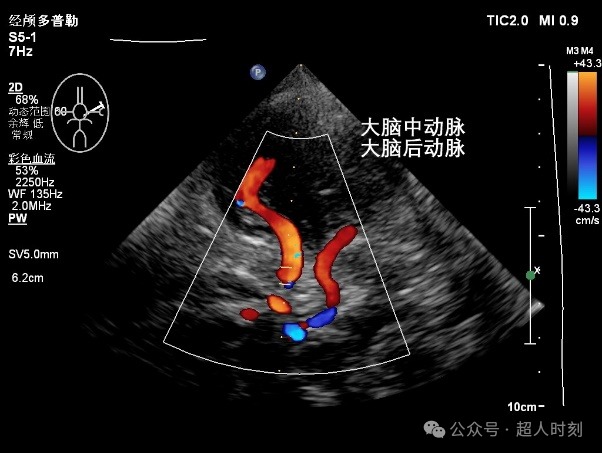

TCCD(图3)不仅能够得到TCD那样的频谱图,还能直观看到血管的走行和血流的状态,是可视化医学的一个明显特征。

图3a

图3b

图3c